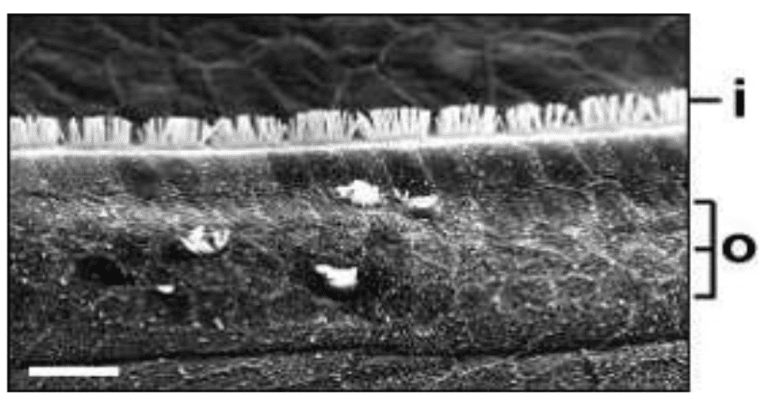

(Based on a lecture by Professor Ali Danesh)

The provided lecture outlines, website excerpts, and research findings collectively discuss the anatomy and physiology of the human ear, specifically focusing on hearing hair cells within the cochlea and the mechanisms of hearing. The sources explore the causes and statistics of hearing loss, including noise exposure, genetics, and ototoxic medications, and differentiate between types of hearing loss. A significant portion addresses hair cell regeneration, examining its occurrence in animal models like birds and the limited capacity in mammals. Finally, the materials investigate potential treatments such as gene therapy targeting genes like Atoh1 and drug therapies inhibiting the Notch pathway to stimulate hair cell regrowth.